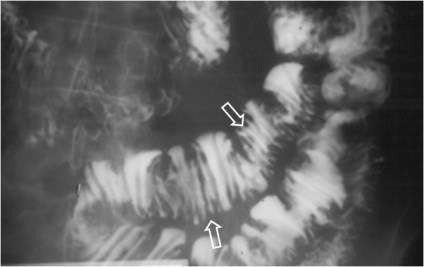

Recibe este nombre el aspecto de los pliegues intestinales engrosados, lisos, rectos y perpendiculares al eje longitudinal de la luz en el estudio del tránsito intestinal baritado. El signo se presenta cuando existe infiltración difusa de la submucosa por edema o hemorragia intramural (traumatismo, isquemia, toma de anticoagulantes, etc).

El aspecto de los pliegues en pila o columna de monedas es más evidente en el yeyuno que en el íleon, debido al mejor desarrollo y mayor tamaño de los pliegues yeyunales.

Por el aspecto de los pliegues intestinales, este signo también se ha denominado Signo de los pliegues en empalizada o en hilera de estacas.

Otro ejemplo de este signo.